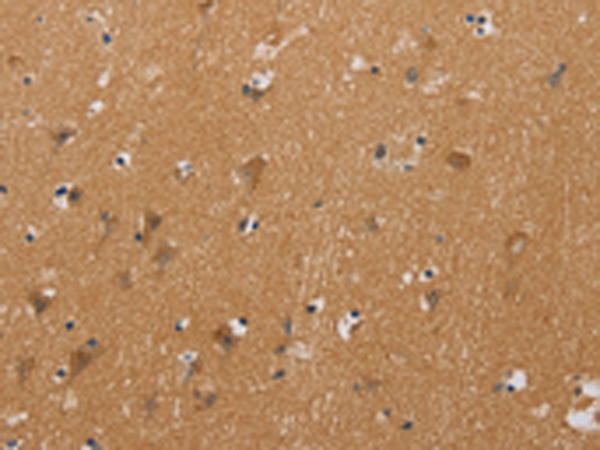

分类: 科研抗体货号: P07432别名: GMA; S-MAG; SIGLEC4A; SIGLEC-4A应用: WB,IHC反应种属: Human, Mouse, Rat